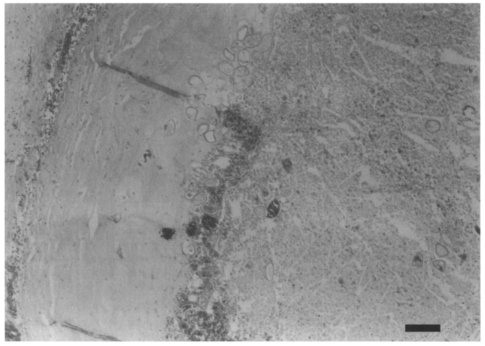

The masses surrounding the lesions in the temporo-occipital lobe were resected on May 20, 1997 and then in the frontal lobe on June 8, 1997 through the craniotomies. The resected masses were yellowish and looked like a branch of grape. Paragonimus westermani eggs were identified under light microscope from the stamp smears of the resected tissues (Fig. 2). The eggs were 81.6 ± 2.9 µm in length and 52.8 ± 2.0 µm in width. This case was diagnosed to be a cerebral paragonimiasis by P. westermani eggs. Pathologic preparations revealed the P. westermani eggs were concentrated near a border of the fibrous worm capsule and scattered in the calcified nodular lesions (Fig. 3). Any remnant of P. westermani was not found in the necrotic worm capsule, except for the eggs.